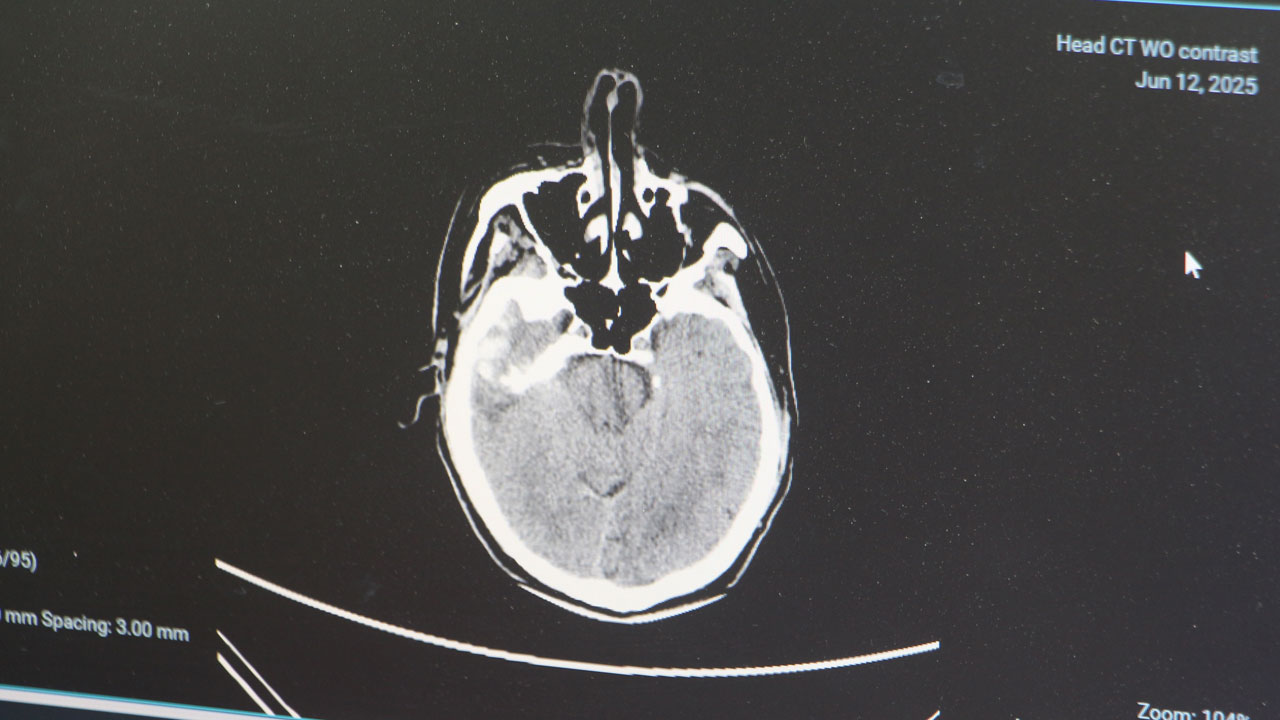

Uzman isimden korkutan açıklama! Bu hastalık gençler arasında yaygınlaşmaya başladı

Eskiden daha çok 50 yaş üzerindekilerde görülen beyin kanamaları, stres, yanlış beslenme ve tansiyon yüksekliği sebebiyle artık gençlerde de sıkça görülüyor.

Adana Şehir Hastanesi Beyin ve Sinir Cerrahisi Bölümü’nden Doç. Dr. Ali İhsan Ökten, gençler arasında giderek artan beyin kanaması vakalarına dikkat çekerek uyarılarda bulundu.

Genellikle 50 yaştan sonra görülen beyin kanaması, son yıllarda gençlerde daha sık görülmeye başlandı. Sebeplerine dikkati çeken Adana Şehir Hastanesi Beyin ve Sinir Cerrahisi Bölümü’nden Doç. Dr. Ali İhsan Ökten, bunların daha çok ‘arteriyovenöz malformasyon’ ve ‘anevrizma’ kaynaklı yaşandığını söyledi. Anevrizma, yani kan damarlarının duvarında oluşan baloncuk şeklindeki patolojik genişlemeler kaynaklı yaşanan beyin kanamalarının 100 binde 10 ile 15 kişi arasında görüldüğünü dile getiren Doç. Dr. Ali İhsan Ökten, “Gençlerde görülme oranı giderek artıyor” dedi.